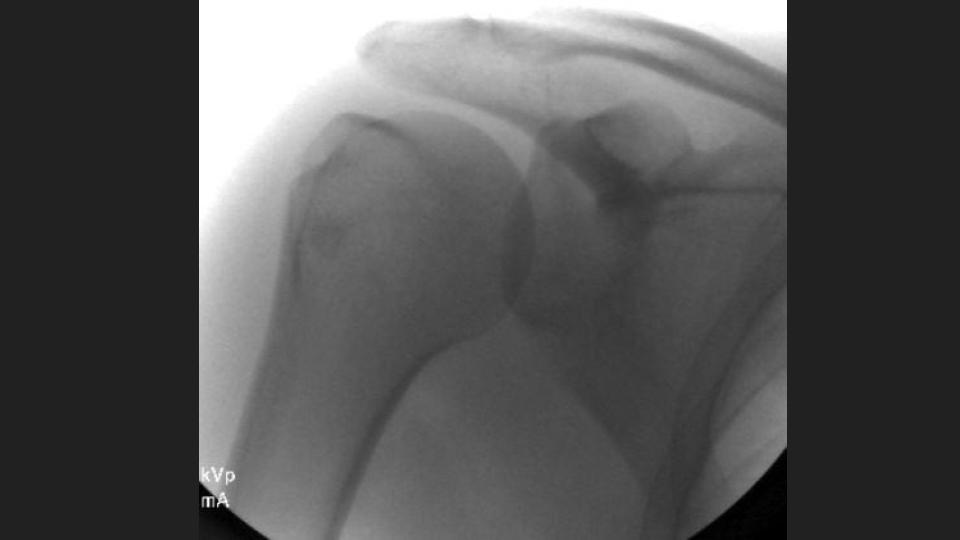

36M with chronic pain and limited motion 3 years after work related injury

My colleague had to share this with me after a failed attempt at arthrography. He puts the shoulder in Grashey, but it doesnt really look like Grashey. No matter what, he couldnt get in and converted it to a routine MRI. The first set of Cor images look so nice....or do they? The crazy thing is that the injury was 3 years ago. Not all workers comp is bogus. I was taught the posterior shoulder dislocation locks the shoulder in internal rotation, but based on the axial image, it is not. 1) Why is that? 2) I think thats partly why the scout image for the arthrogram was so misleading.

dislocation ( RID4770 )